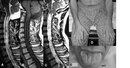

Malign tümörler, kanserli hücrelerin kontrolsüz bir şekilde bölünmesi ve çoğalması sonucu oluşan, çevre dokulara zarar verebilen ve metastaz yapma potansiyeline sahip olan tümörlerdir. Bu tümörler, vücutta çeşitli sistemleri etkileyebilir ve ciddi sağlık sorunlarına yol açabilir. Bu makalede, malign tümörlerin belirtileri, tanı yöntemleri ve tedavi seçenekleri ele alınacaktır. Malign Tümörlerin BelirtileriMalign tümörlerin belirtileri, tümörün türüne, büyüklüğüne ve bulunduğu bölgeye göre değişiklik gösterebilir. Ancak, genel olarak aşağıdaki belirtiler sıkça gözlemlenmektedir:

Bu tanı yöntemleri, malign tümörlerin varlığını belirlemek ve tümörün türünü, evresini değerlendirmek amacıyla kullanılmaktadır. Erken tanı, tedavi sürecinde büyük bir öneme sahiptir. Malign Tümörlerin Tedavi SeçenekleriMalign tümörlerin tedavisi, tümörün türüne, evresine ve hastanın genel sağlık durumuna bağlı olarak değişiklik göstermektedir. Başlıca tedavi yöntemleri şunlardır:

Bu tedavi yöntemleri, genellikle bir arada kullanılarak uygulanmakta ve hastanın durumuna en uygun tedavi planı oluşturulmaktadır. SonuçMalign tümörler, ciddi sağlık sorunlarına yol açabilen ve erken tanı gerektiren hastalıklardır. Belirtilerin farkında olmak, erken tanı ve tedavi sürecini başlatmak için önemlidir. Tedavi seçenekleri, hastanın genel sağlık durumu ve tümörün özelliklerine göre değişiklik göstermektedir. Bu nedenle, malign tümör belirtileri görüldüğünde mutlaka bir sağlık uzmanına danışılmalıdır. Ekstra BilgilerMalign tümörlerin önlenmesi için sağlıklı yaşam tarzı, dengeli beslenme, düzenli egzersiz ve sigara gibi zararlı alışkanlıklardan uzak durmak önemlidir. Ayrıca, düzenli sağlık kontrolleri ve tarama testleri, erken tanı ve tedavi için kritik bir rol oynamaktadır. Kanserle ilgili farkındalığın artırılması ve eğitim programları, toplumda kanserin önlenmesi ve erken tanınması konusunda büyük fark yaratabilir. |